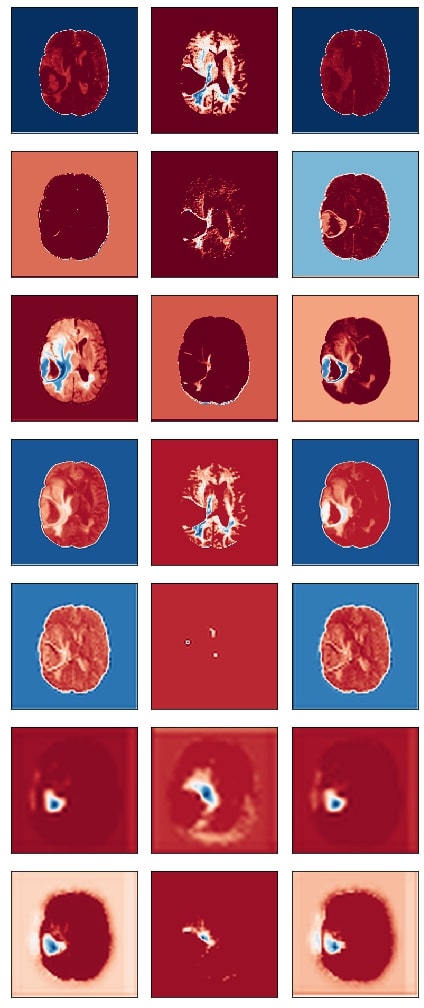

9.2 Network Dissection

Final extracted disentangled concepts for different filters of a particular layer are shown. The figures clearly show that different filters are specialized to detect different concepts of the input image. All three networks show similar behaviour.

Refer to caption

Figure 9: Concepts learned by filters of a particular layer of the ResUnet for an input image. (Conv Layer 21)

Figure 10: Concepts learned by filters of a particular layer of the DenseUnet for an input image. (Encoding Block 1, Conv 2)